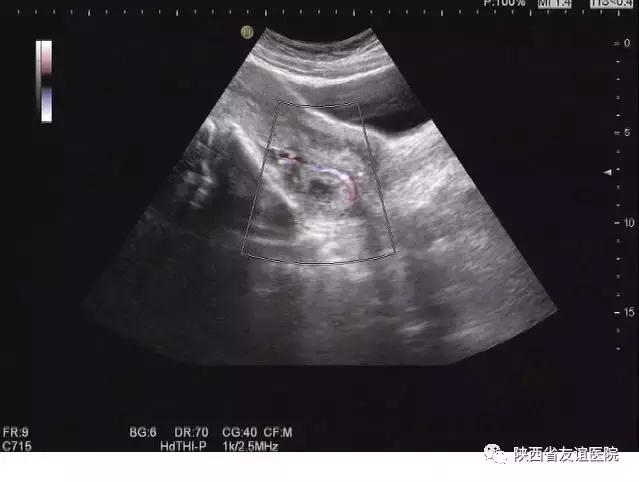

宫外孕B超图

其实,这些想法都是不对的。孕早期是排除宫外孕和胚胎是否正常发育的关键时期,早期的检查可以明显地降低事故的发生率。在平时的检查中,经常会看到这样一些孕妇,来产检时是以孕12周伴阴道出血来就诊的,但是B超显示的发育程度与孕周明显不符,甚至出现了胚胎停育的现象;还有一些人甚至有严重的腹痛及阴道出血,并伴有休克,甚至危及生命,经B超检查诊断为宫外孕破裂,。而这些人中,很多是第一次进行B超检查的。